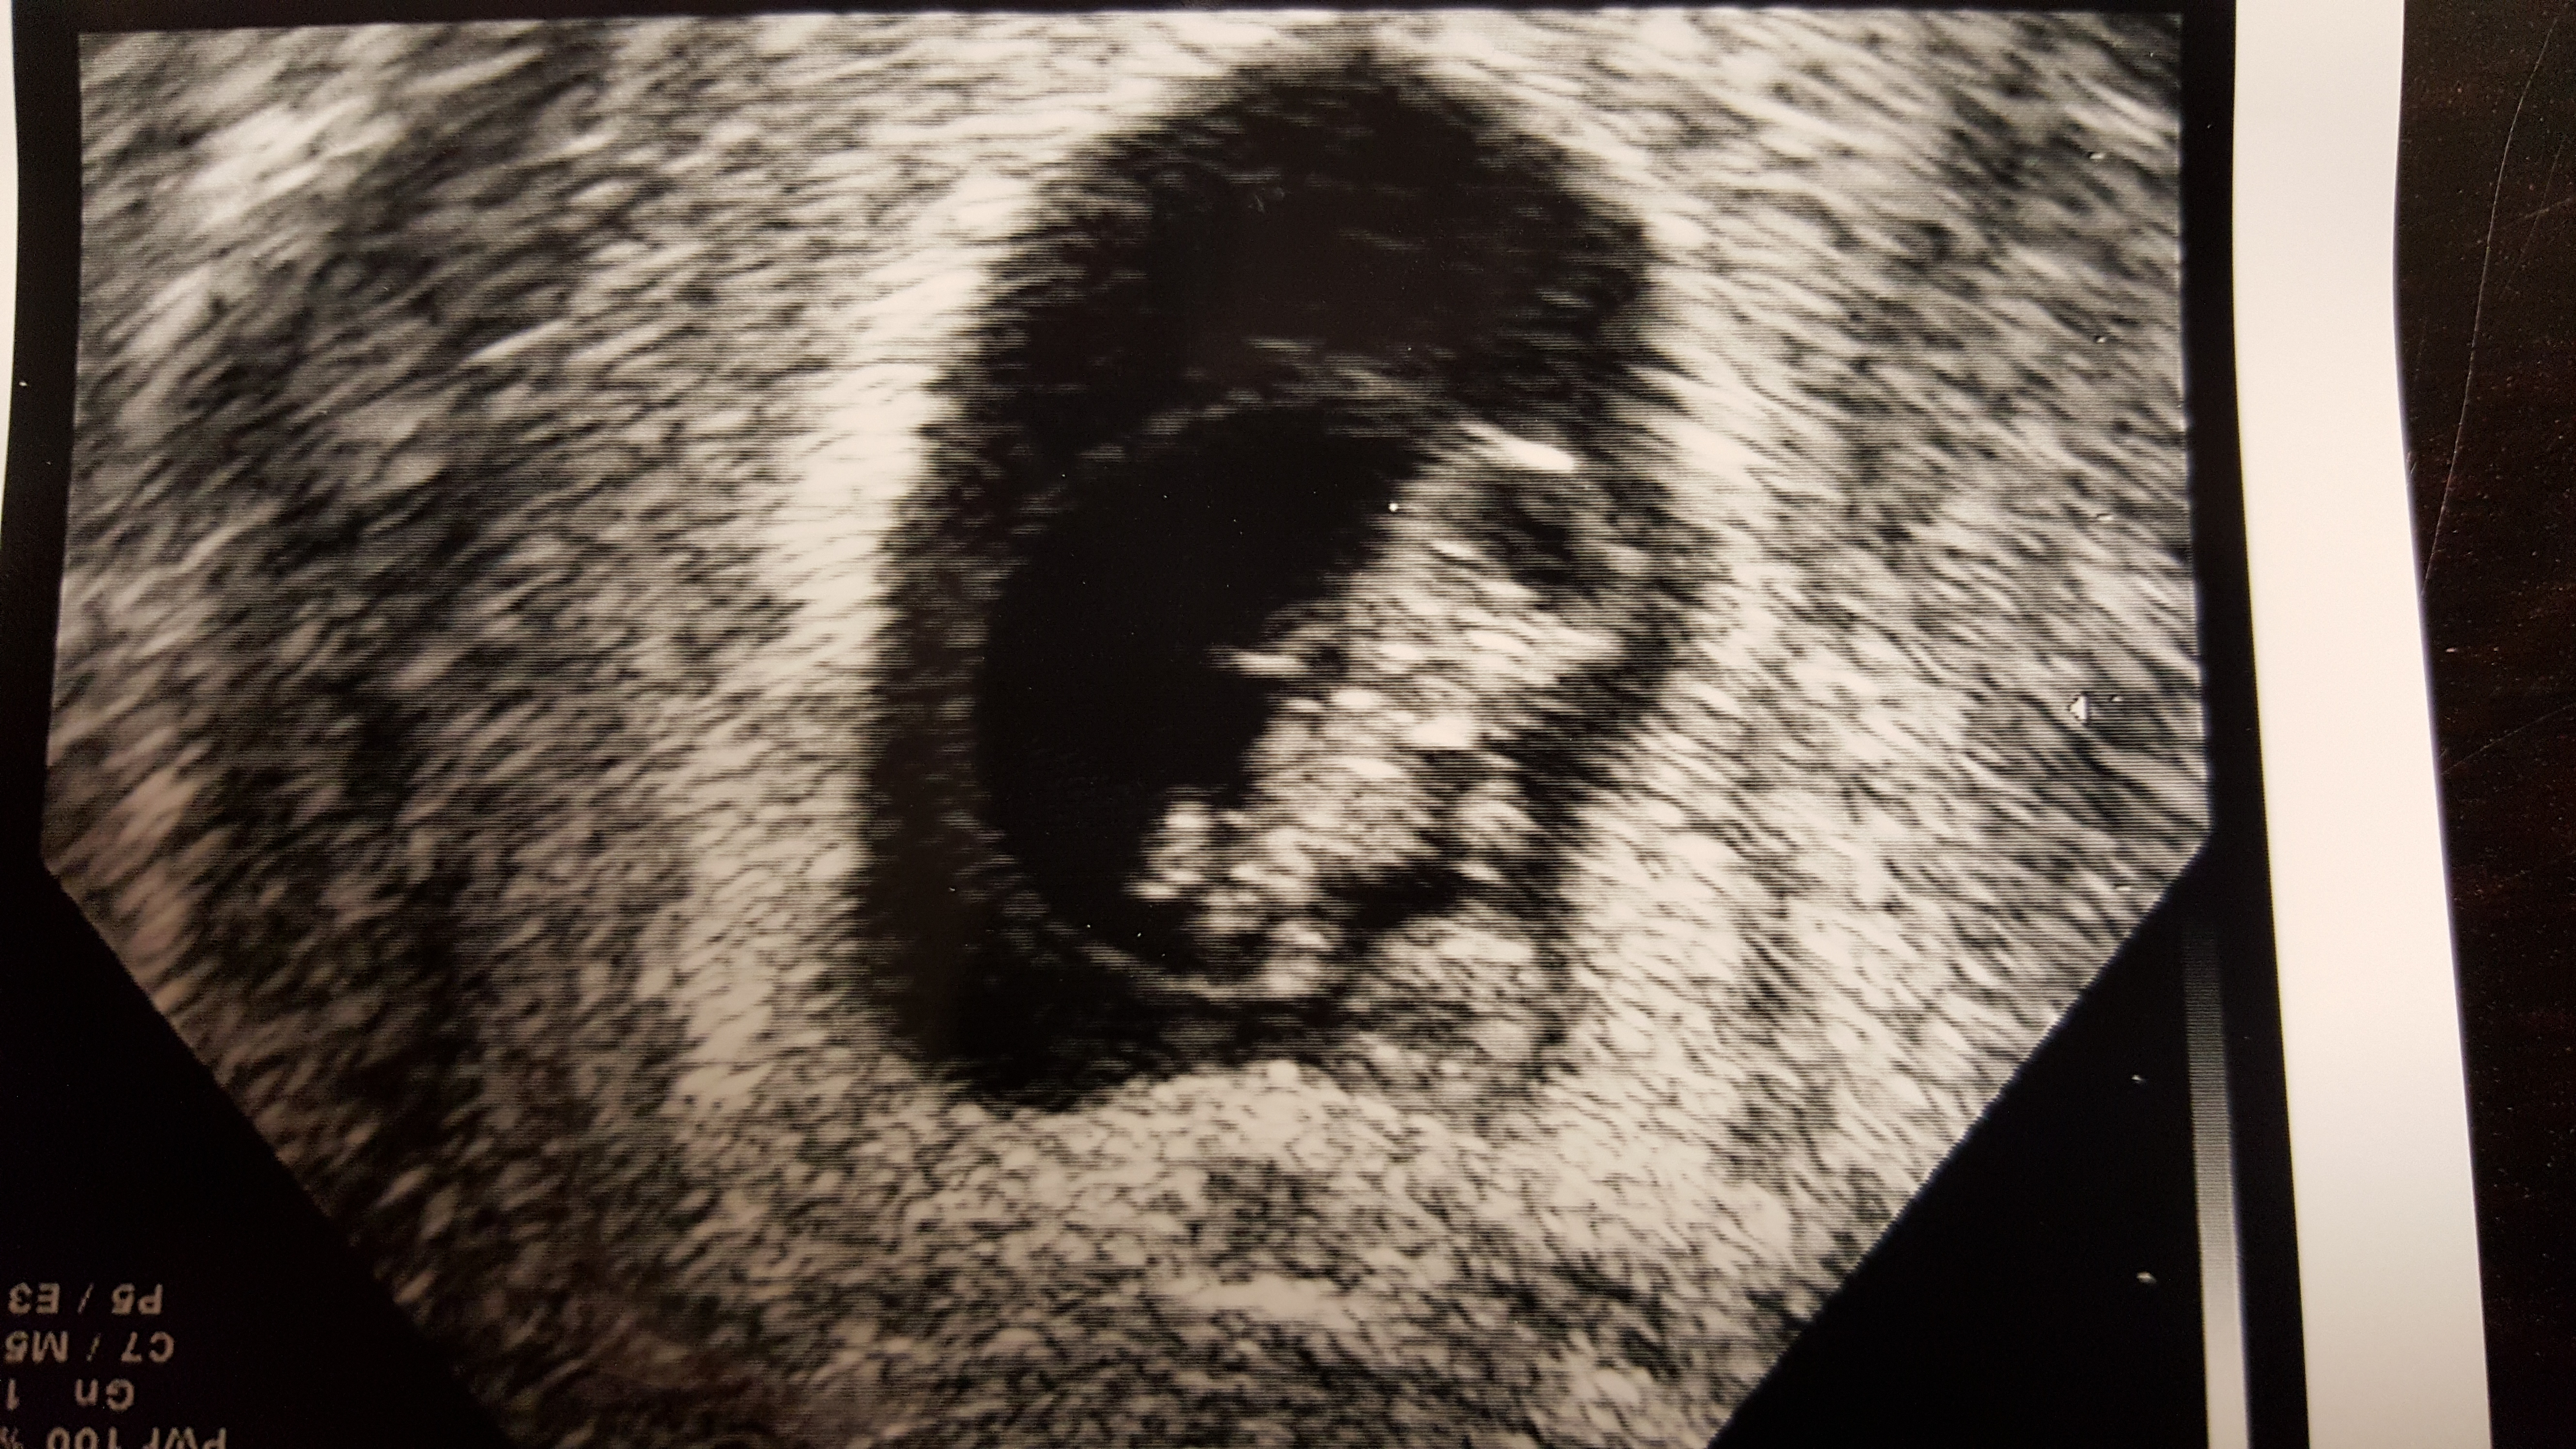

I had my second u/s on Tuesday at 8 weeks and 6 days. The baby is still measuring three days behind but they have not changed my edd. It was great to see how big the baby has gotten and to see its heart still beating. I go back on the 23 for some genetic testing and I get an u/s at that appointment, which was a great surprise to hear that. The equipment at the new place I have to go to is so much better than what my doctor has. Im hoping I can actually hear the heart beat at that appointment. I have not been able to hear it or to know how many bpm it is. But here is my little bean!

Btw I have no clue what those white lines are and neither does my doctor.

Not a great photo, but we saw the little flicker of the heartbeat!